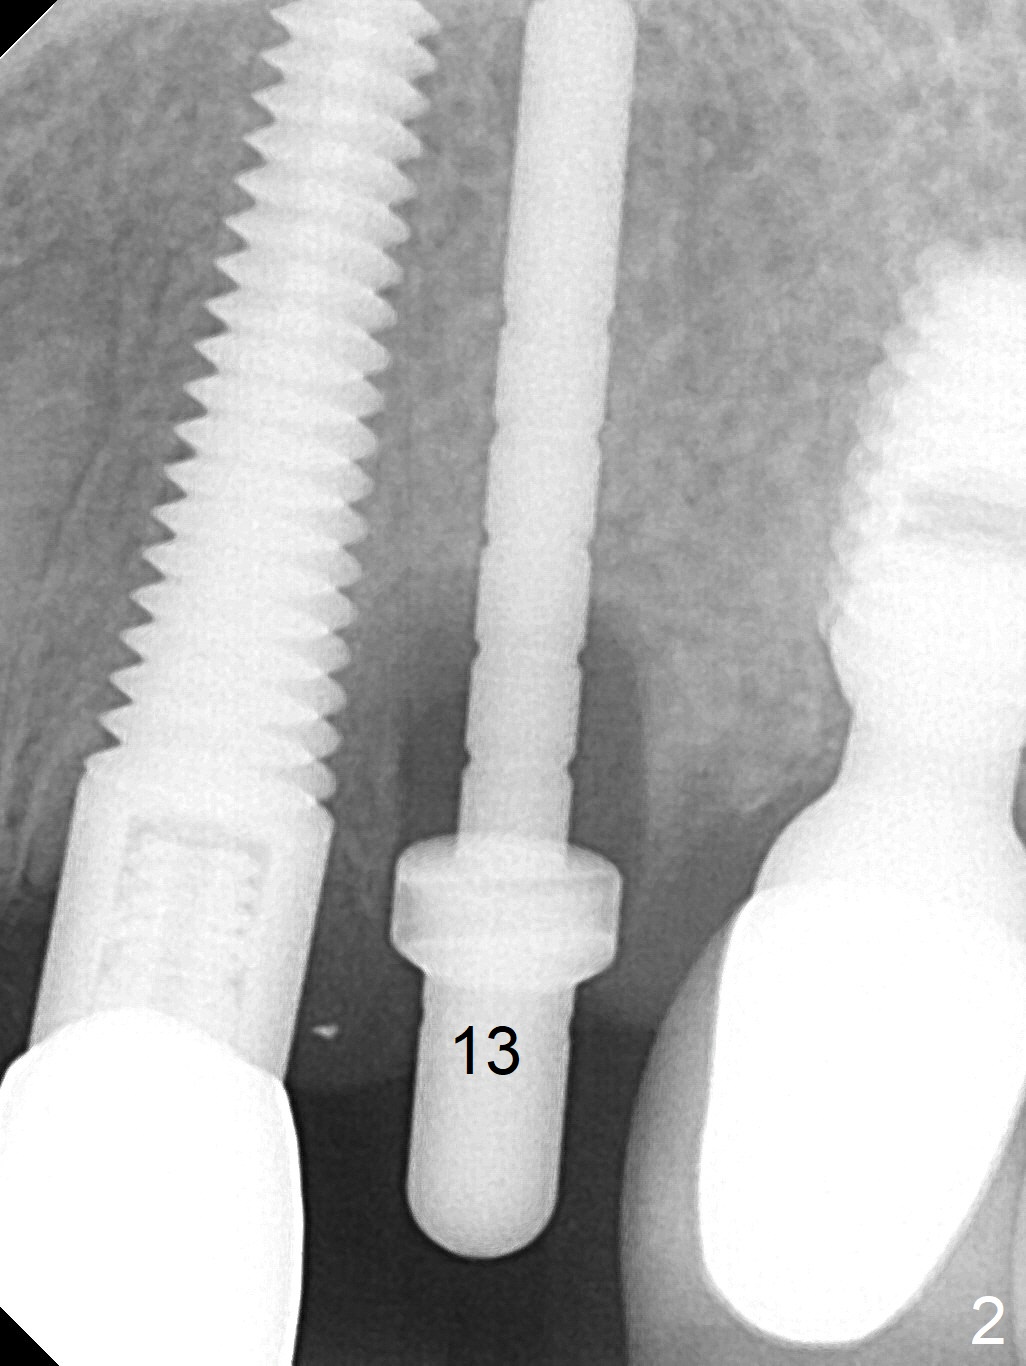

The root of the tooth #13 has an oblique fracture as related to a prefabricated post after 9 years of service (Fig.1). The trajectory of the initial osteotomy (Fig.2) is corrected with Lindamann bur and reuse of 2 mm drill (Fig.3). A 4x20 mm tissue-level implant is placed with > 60 Ncm, followed by tightening a 3.5x5 mm abutment (Fig.4,5); the mesiobuccal defect being filled with Vera Graft (Fig.4 *). An immediate provisional is fabricated. It appears that the implant should have been placed deeper (Fig.6: 5 months postop).